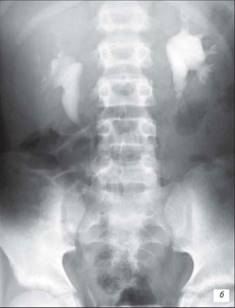

Екскреторна урограма (15‑а хвилина)

Гіпоплазія правої нирки – вона невеликих розмірів, чашки зближують, шийки їх укорочені, форнікси деформовані